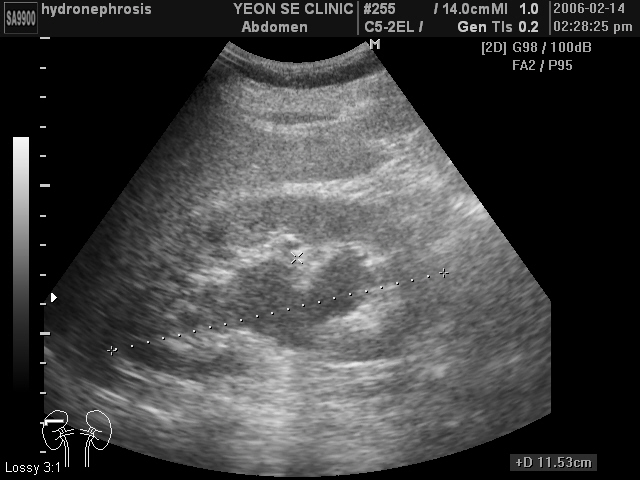

Ultrasonographic data of our patients

Hydronephr...